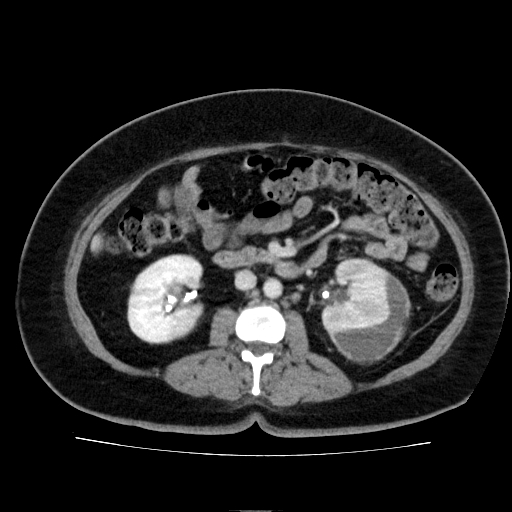

El estudio demuestra que el riñón izquierdo se encuentra aumentado de tamaño, con realce heterogéneo del parénquima renal en las fases corticomedular y nefrográfica, hallazgos compatibles con cambios inflamatorios secundarios a pielonefritis. Asociado a estos hallazgos, se identifica colección perirrenal localizada en la cara posterior del riñón izquierdo, con densidad líquida aproximada de 20 UH y paredes que realzan con el medio de contraste, con dimensiones aproximadas de 32 × 72 × 108 mm y volumen estimado de 130 cc, compatible con absceso perirrenal.

Se observa además presencia de catéter doble J en ambos sistemas colectores, con adecuada excreción del medio de contraste y sin evidencia de dilatación ureteral ni del sistema pielocalicial.

El riñón derecho presenta realce levemente heterogéneo, sugestivo de cambios inflamatorios residuales por pielonefritis previa, sin evidencias de colecciones ni lesiones focales.

Entre los hallazgos adicionales se identifican cambios inflamatorios en la grasa pararrenal izquierda con adenomegalias reactivas, engrosamiento difuso de las paredes vesicales compatible con cistitis, hepatomegalia leve, y engrosamiento difuso de las paredes gástricas sugestivo de gastritis.